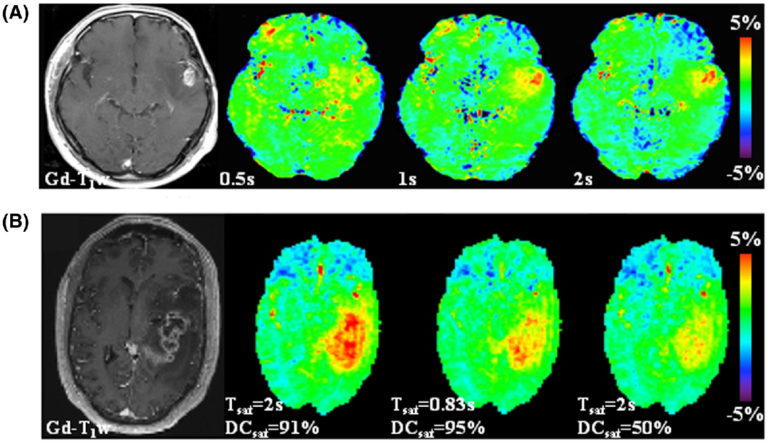

MRM : https://doi.org/10.1002/mrm.29241 CEST MRI provides many different clinically promising contrasts. The best studied is Amide Proton Transfer-weighted (APTw) CEST MRI in brain tumors. However, even for APTw in brain tumors many protocols are out there, often with different rf saturation powers, rf duty-cycles and durations, or with different post processings and visualizations. In this […]MRM : https://doi.org/10.1002/mrm.29241 CEST MRI provides many different clinically promising contrasts. The best studied is Amide Proton Transfer-weighted (APTw) CEST MRI in brain tumors. However, even for APTw in brain tumors many protocols are out there, often with different rf saturation powers, rf duty-cycles and durations, or with different post processings and visualizations. In this […]